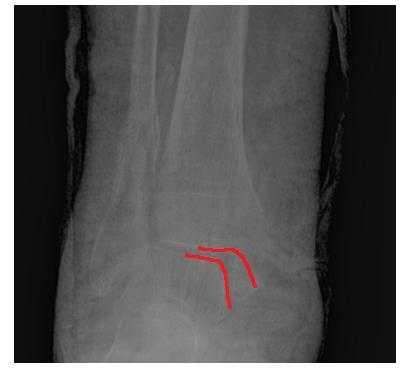

По достижении обезболивающего эффекта производится закрытая ручная репозиция перелома таранной кости с устранением грубых смещений отломков. При этом особое значение мы придаем устранению ротационного смещения переднего отломка таранной кости. С этой целью передний отдел стопы переводится в положение умеренной пронации. Затем в большеберцовую кость, на уровне ее нижней трети, вводят два винта Шанца и проводят спицу, которые закрепляют в кольцевой (или кольцевых) опоре аппарата. Через пяточную кость, перпендикулярно сагиттальной плоскости, проводят две спицы и закрепляют в заднем полукольце замкнутой опоры. Через кости среднего отдела стопы, не нарушая ее поперечного свода, проводятся две перекрещивающиеся спицы, которые закрепляются в переднем полукольце той же опоры. Опоры соединяются между собой резьбовыми стержнями с шарнирами. Перемещением по резьбовым стержням осуществляют дозированную дистракцию, поворотом переднего полукольца замкнутой опоры по шарнирам в направлении пронации переднего отдела стопы производят репозицию перелома таранной кости. При значительных по величине смещениях таранной кости производится открытая репозиция из малых операционных доступов с устранением всех видов смещений под визуальным контролем. По завершении репозиции, изолированно, через каждый отломок таранной кости проводят спицы, которые закрепляют в кронштейнах, установленных на замкнутой опоре. Операция завершается контрольной рентгенограммой голеностопного сустава в двух стандартных проекциях и рентгенограммой стопы в проекции на таранную кость. Срок лечения в аппарате составляет 2,5-3 месяца.

Переломы и переломо-вывихи блока таранной кости относятся к числу наиболее тяжелых и трудно репонируемых переломов костей конечностей. Как правило, при лечении таких переломов открытое вправление фрагмента (фрагментов) блока таранной кости является наиболее оптимальным. Оперативный доступ осуществляется по боковой или передне-боковой поверхности области голеностопного сустава соответственно смещенному фрагменту блока таранной кости. После репозиции и вправления блока последний временно фиксируется короткими спицами. При таких повреждениях применяется разработанная нами компоновка аппарата внешней фиксации (Патент РФ на полезную модель №63671), а также способ лечения переломов таранной кости (Патент РФ на изобретение №2356511).

Компоновка аппарата также состоит из одной или двух кольцевых опор голени и замкнутой опоры стопы, соединенных шарнирно-резьбовыми системами. Введение винтов Шанца и проведение спиц через большеберцовую, пяточную и кости среднего отдела стопы производится по описанной методике. По достижении репозиции с устранением всех видов смещений через отломки таранной кости проводят спицы и закрепляют в замкнутой опоре аппарата. Аппарат переводится в режим стабильной фиксации. Рана закрывается по общехирургическим правилам. Операция завершается контрольной рентгенограммой голеностопного сустава в двух стандартных проекциях и рентгенограммой стопы в проекции на таранную кость. Срок лечения в аппарате составляет 3 месяца.